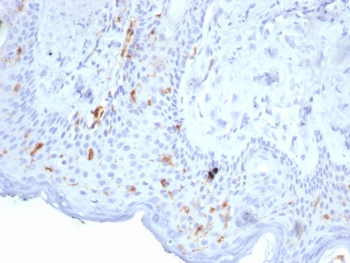

Langerhans cells (LCs) are a subset of immature dendritic cells (DCs) that specifically localize in the epidermis and other mucosal epithelia. Epidermal LCs possess strong immuno-stimulatory capacity and play a central role in the initiation and regulation of immune responses. Langerin (CD207) is a Ca2+-dependent, C-type lectin domain containing, type II transmembrane protein that induces epidermal LCs to differentiate into Birbeck granules (BG). BGs are organelles with superimposing and zippering membranes that influence proper class I type antigen presentation to the circulating T cells. Human spleen, lymph node, thymus, liver, lung and heart express Langerin protein.